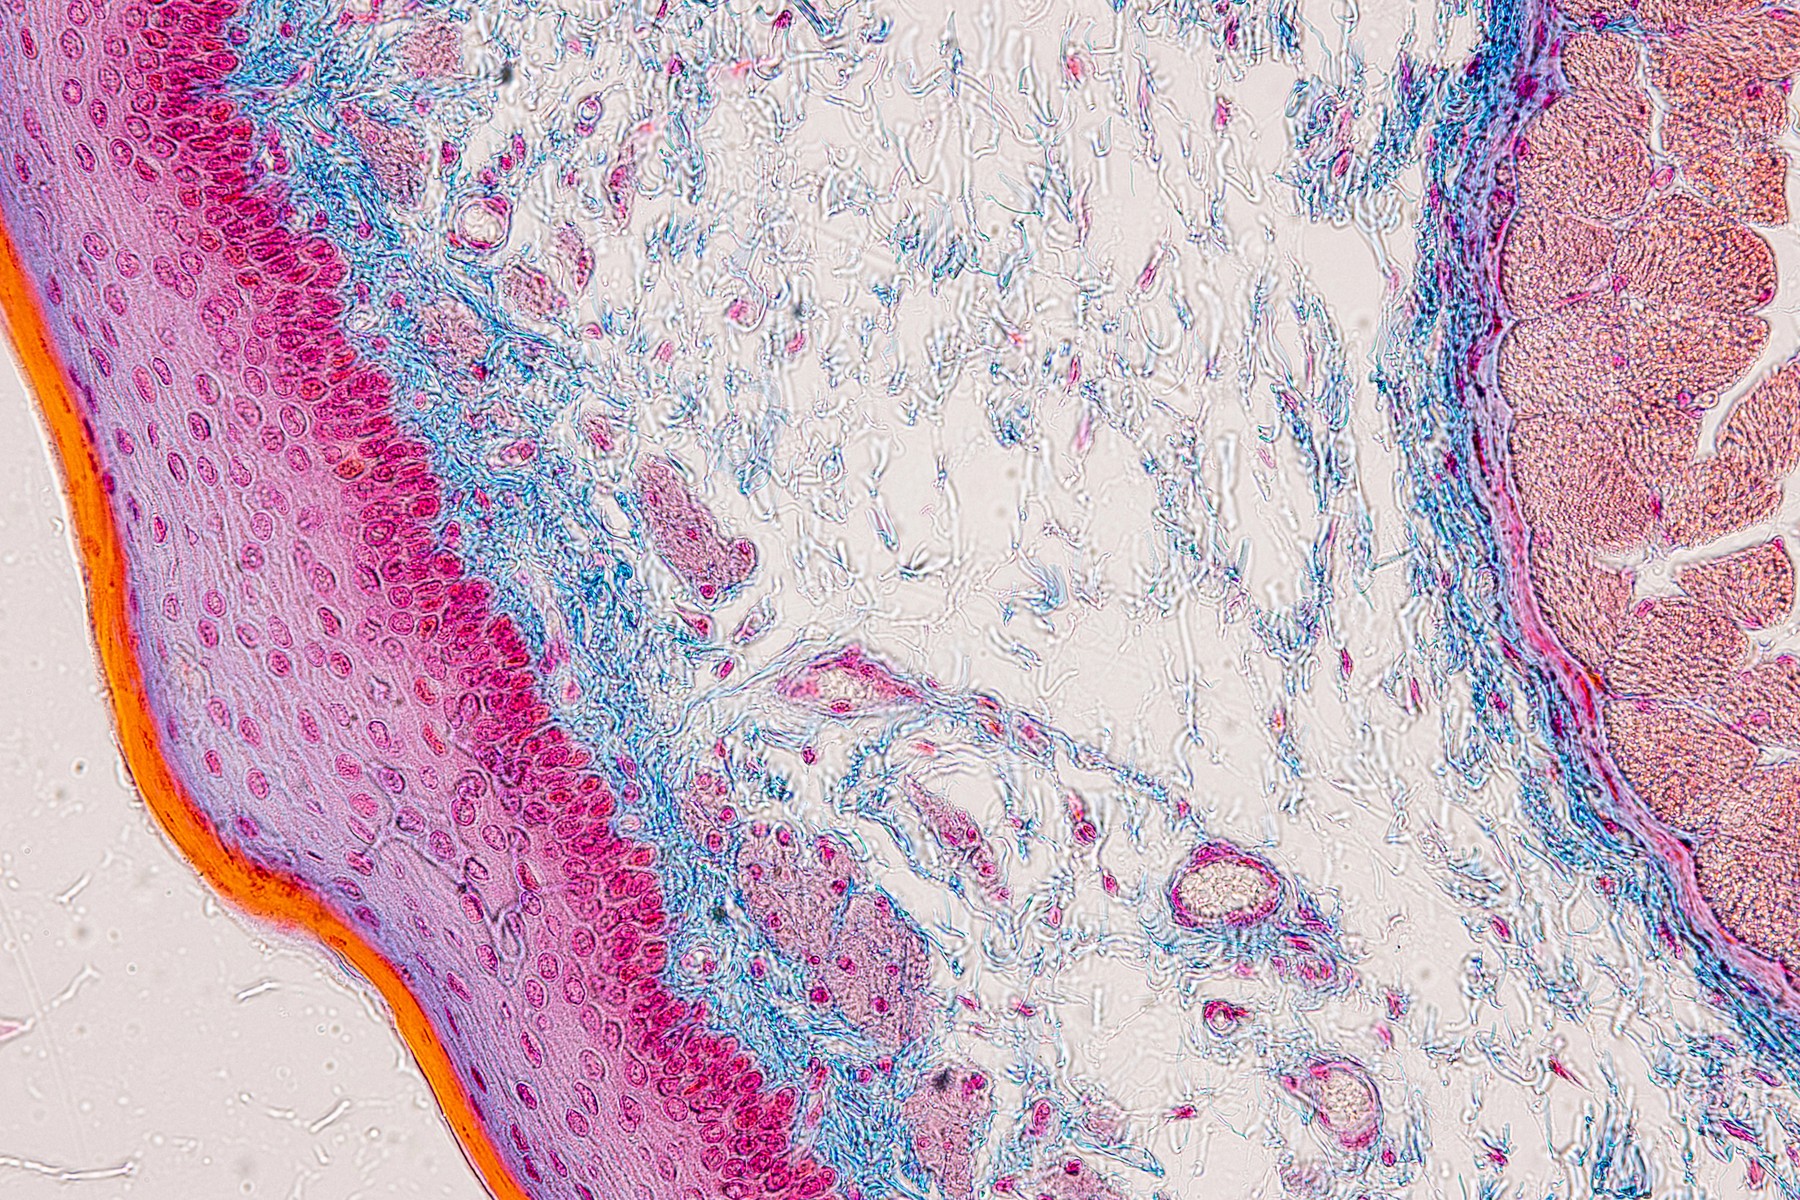

Alfred Kohn byl prvním lékařem-vědcem, který označil příštítná tělíska jako samostatný endokrinní orgán. Pro soubory chromafinních buněk zavedl pojem „paraganglia“. Jeho studie se také týkaly hypofýzy, intersticiálních buněk varlat a vaječníků. Za svůj život napsal 50 vědeckých prací.